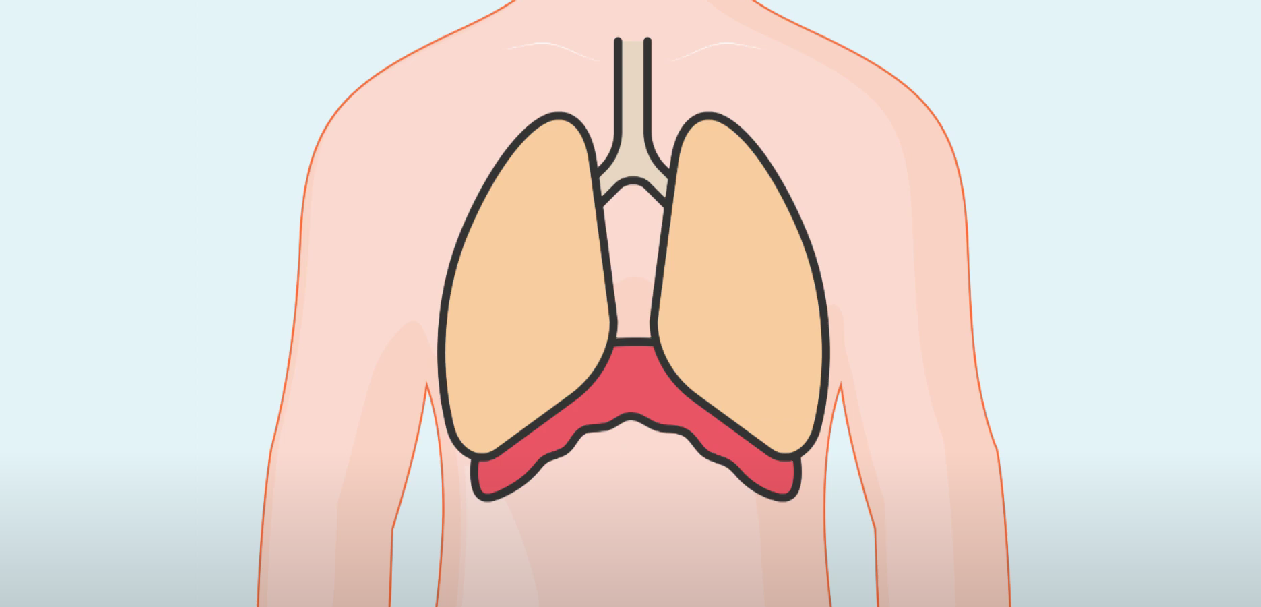

가슴과 배 사이에 있는 '횡경막'이 자극되어

경련이 일어나서 하게 되는데요.

이 경련으로 인해 성대가 갑자기 닫혀서

공기가 들어가지 못해

특유의 딸국질 소리가 나게 됩니다.